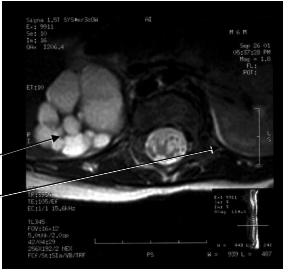

Horseshoe Kidney

Horseshoe Kidney (1/600) is usually asymptomatic and forms when the bilateral metanephric blastema get stuck together in the midline. Because the inferior mesenteric artery comes off of the ventral side of the aorta in the lower abdomen, the now horseshoe-shaped kidney gets caught under this vessel and cannot rise up to its normal location along the dorsal, retroperitoneal wall of the abdomen.